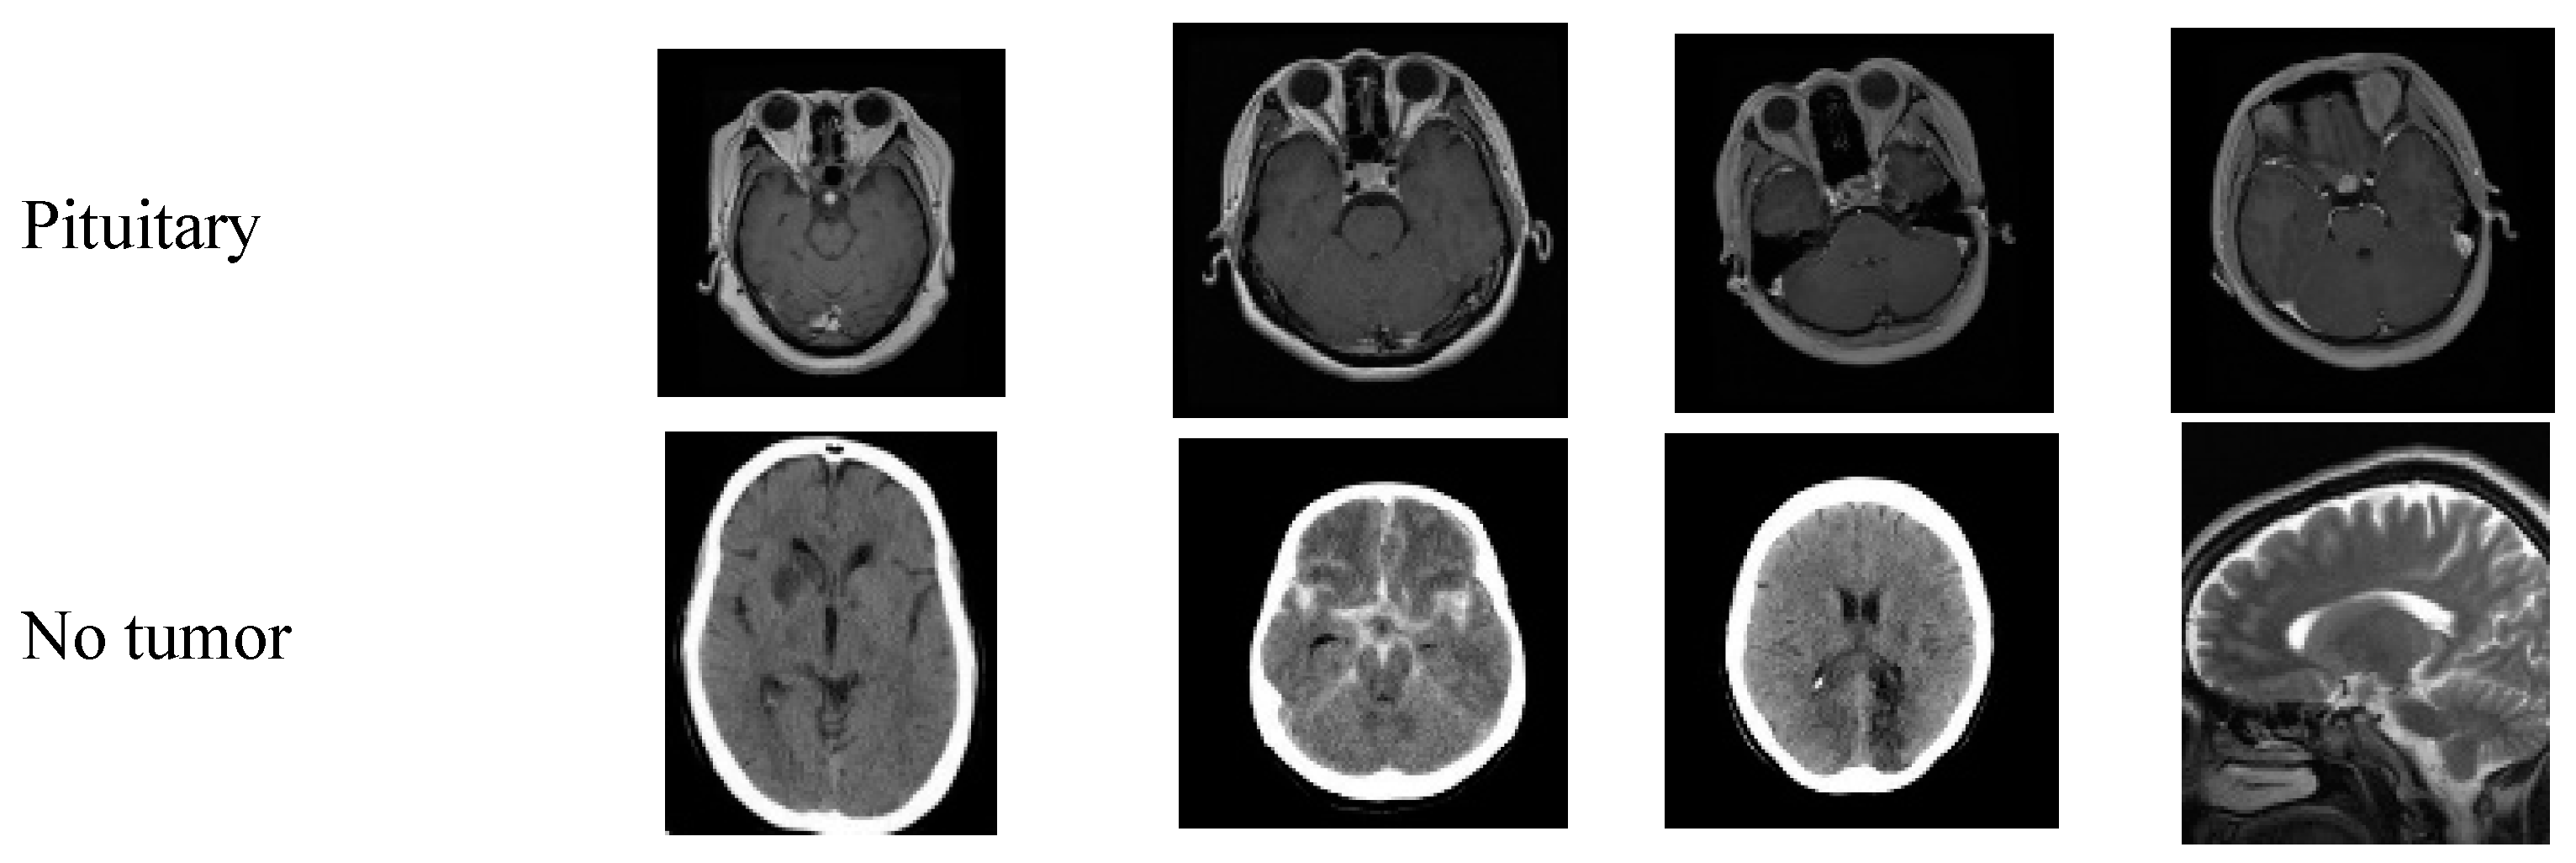

4.7. Dataserts Sample Images

Figure 4 shows the sample images of every class; the first row represents the sample MR images of class glioma, the second row has the meningioma class, the third row represents the pituitary class, and the fourth row represents the no tumor class. The images used in the no tumor class were obtained from the Br35H dataset. This dataset offers an extensive and varied collection of images to train and evaluate the models used in this study, enabling a more comprehensive analysis of the effectiveness of the models. Figure 4 displays a small selection of images from the dataset presented.

Figure 4. Sample images of the utilized dataset.

Brainsci 14 01178 g004aBrainsci 14 01178 g004b